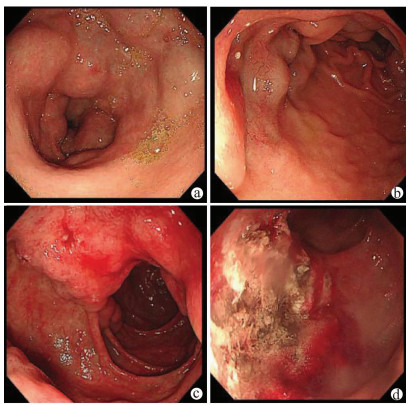

Value of SpyGlass single-operator choledochoscopy system in the diagnosis and treatment of patients with biliary tract diseases

Si ZHAO, Xueru WU, Linlin YIN, Lin MIAO, Guozhong JI, Xiuhua ZHANG

2021, 37(10): 2395-2399. DOI: 10.3969/j.issn.1001-5256.2021.10.027

Abstract(2477) HTML (634) PDF (2327KB)(122)

Abstract:

Objective  To investigate the value of SpyGlass single-operator choledochoscopy system in the diagnosis and treatment of patients with unexplained biliary stricture, complex bile duct stones, or other biliary tract diseases.  Methods  A retrospective analysis was performed for the clinical data of the patients with biliary tract diseases who were diagnosed and treated with SpyGlass in The Second Affiliated Hospital of Nanjing Medical University from December 2017 to June 2020. For the patients with biliary stricture, the biliary lesions were fully visualized under the guidance of SpyGlass, and SpyBite biopsy was performed if necessary; the patients with bile duct stones were treated with SpyGlass-guided direct-view laser lithotripsy; for the patients with gallbladder disease, the cystic duct was superselected with the assistance of SpyGlass. The SpyGlass system was analyzed in terms of its sensitivity, specificity, and accuracy rate in diagnosis and treatment, lithotripsy success rate, stone clearance rate, procedure success rate, and incidence rate of complications.  Results  A total of 58 patients underwent SpyGlass procedure. SpyGlass was used to evaluate biliary stricture of unknown nature in 44 (76%) patients; SpyGlass visual impression had a diagnostic sensitivity of 92% (24/26), a specificity of 94% (17/18), and an accuracy of 93% (41/44), and SpyBite biopsy had a diagnostic sensitivity of 71% (15/21), a specificity of 92% (11/12), and an accuracy of 79% (26/33). SpyGlass was used for the treatment of bile duct stones in 8 patients (14%), with a lithotripsy success rate of 83% (5/6) and a stone clearance rate of 88% (7/8). A guide wire under the SpyGlass system was to superselect the cystic duct in 5 patients (9%), with a procedure success rate of 80% (4/5). In one patient (1%), SpyGlass was used to assist the removal of common bile duct stones after liver transplantation and the treatment of bile duct anastomotic stricture. A total of 5 patients (9%) experienced complications after surgery.  Conclusion  The SpyGlass choledochoscopy system is accurate, safe, and effective in the diagnosis and treatment of unexplained biliary stricture, complex bile duct stones, and other biliary tract diseases.